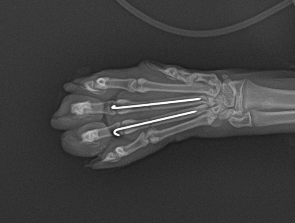

落下の衝撃で指の骨が折れていたため肺の状態の回復を待って骨折の手術も行いました。この症例は翌日退院しております。